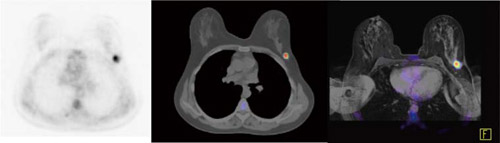

乳がんFDG-PET/CT&MRIのフュージョン